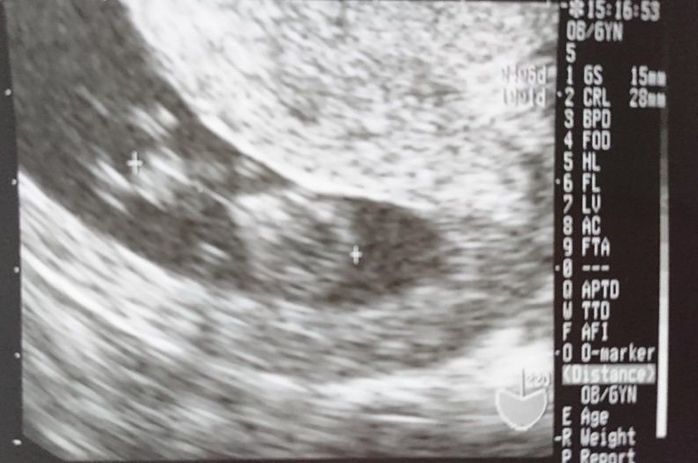

妊娠6週目のエコー写真

12月27日、妊娠したかどうか、モヤモヤした気持ちで年を越したくなかったので、検査に行きました。妊娠が分かった時は、お姉ちゃんと5歳も離れていたので、本当に嬉しかったです。サンタさんに少し遅れたクリスマスプレゼントをもらったような気がしました。赤ちゃんの袋の中に卵黄嚢が見えました。